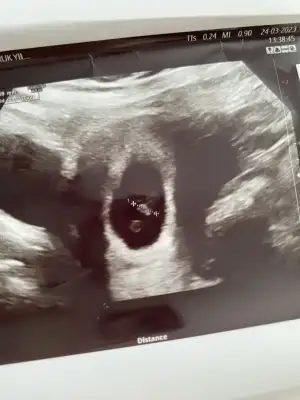

Sanırım bu teori en merak ettiğim teoriBence bebeğin konumu değişebiliyor o yüzden parlak alana odaklanmalıyız. Seninkinde bebek sağdaydı ama parlak alan net olarak sağda mıydı bi bakar mısın :) Kendimizi geliştirelim![]()